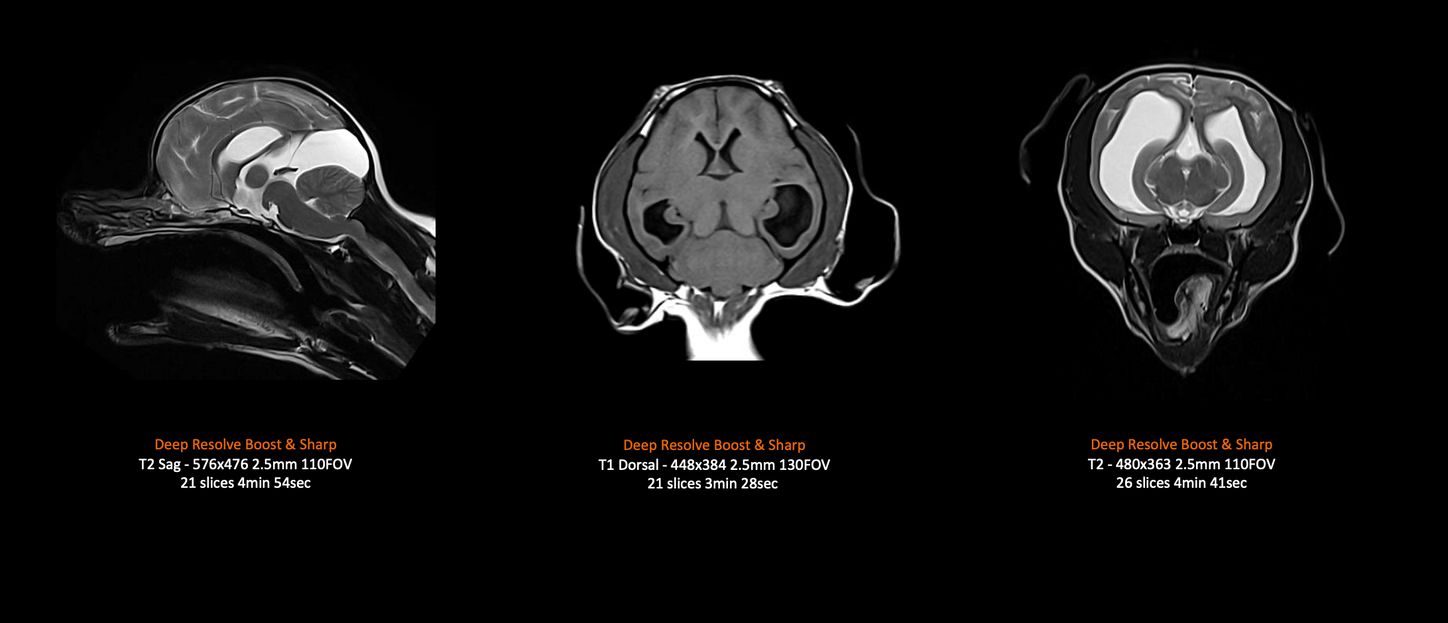

MAGNETOM Free.Max

Canine MRI Brain 14kg.

Images courtesy of Case ID Study ID: UK_MAC_1aaaa5968